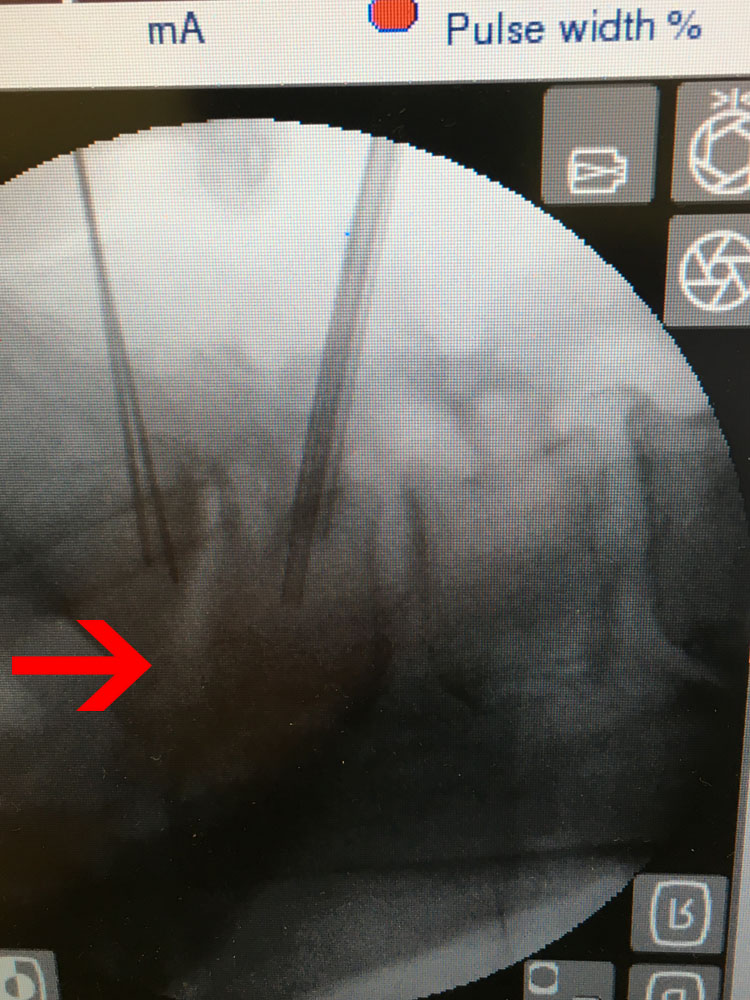

Εικ 3 – (α,β,γ,δ,ε,,στ,ζ,η,θ) Δια-επεμβατικές φωτογραφίες βιοψίας με χρήση του συστήματος πλοηγήσεως O-ARM. Οστικά δείγματα έχουν ληφθεί από το μεσοσπονδύλιο δίσκο Ο5-Ι1 και τους εκατέρωθεν σπονδύλους Ο5 και Ι1.

(ι,ια) Δείγματα οστικά και κυτταρικά.

Τα αποτελέσματα της ιστολογικής και κυτταρολογικής εξέτασης δεν έδωσαν απόλυτα σαφή διάγνωση για το υφιστάμενο παθολογικό υπόστρωμα, ωστόσο οι κυριότερες ενδείξεις ήταν υπέρ φλεγμονής σταφυλοκοκκικής αιτιολογίας.